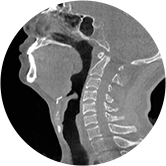

頸椎

氣道三維影像重建